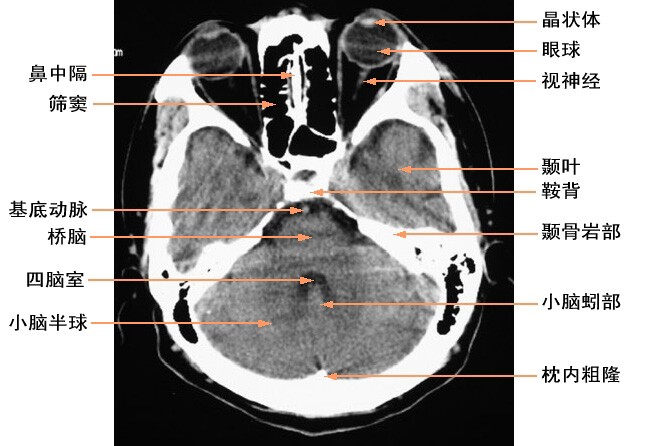

给大家看几个脑部解剖CT图。大家一起学习下。